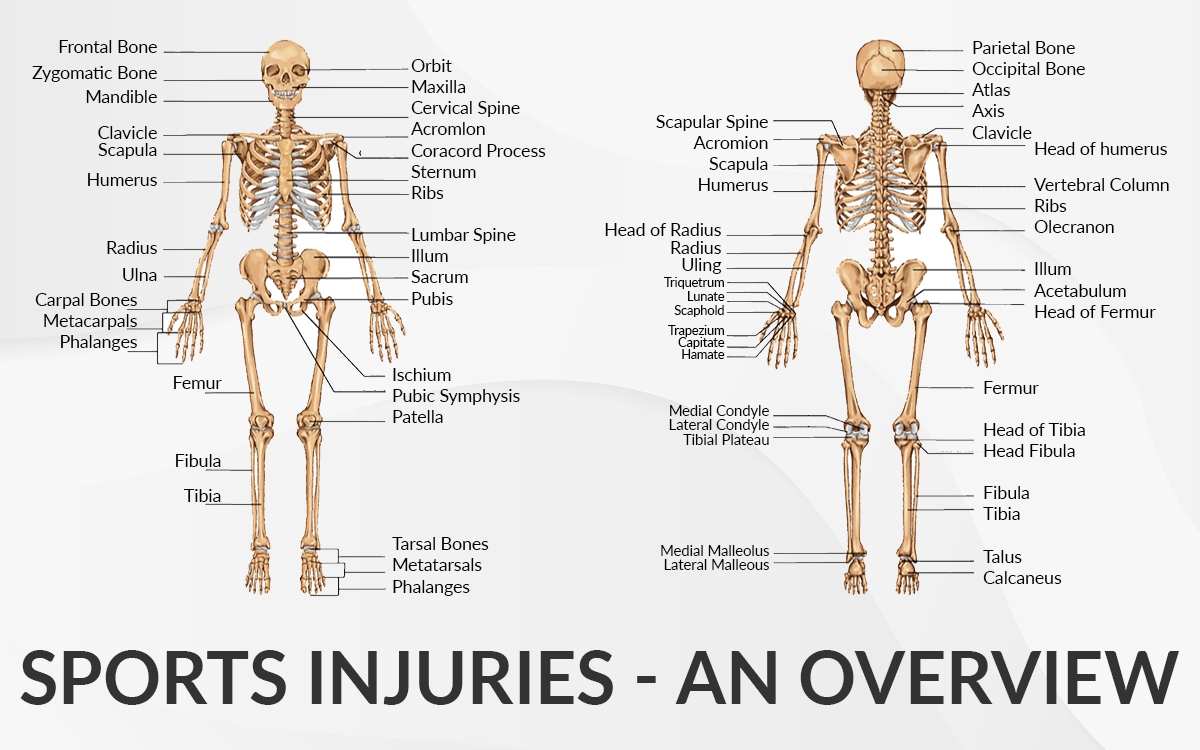

Summary

Common Sports injuries of Hand and Wrist

- Boxer’s Fracture/Metacarpal Fracture/Knuckle Fracture

- Mallet Injury and Fractures

- Skiing – Skiers Thumb (Gamekeepers Thumb)

- Rugby- FDP Tendon and Jersey Finger

- Weight Training/TFCC Injury

Saurabh has a specialist interest in the treatment of sports injuries. Below is a list of some common hand and wrist sports injuries that he has treated in the past.